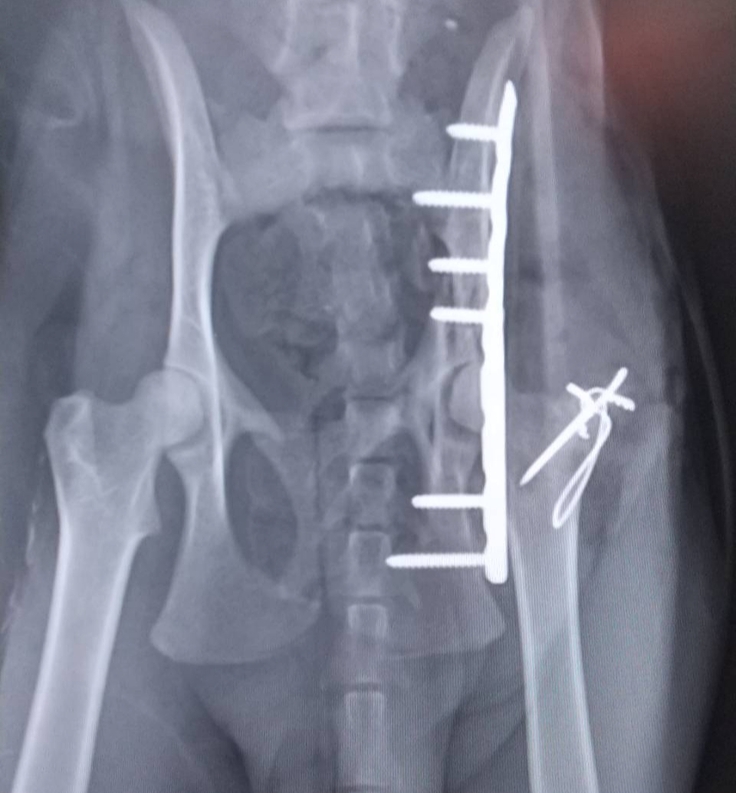

三毛猫ちゃんのレントゲンです

↑手術直後